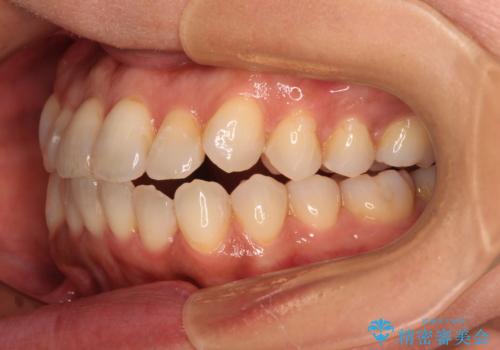

前歯のクロスバイト インビザラインによる矯正治療

- 上下のクロスバイトと前歯のデコボコを気にして来院された患者様です。

インビザラインを用い、IPR(歯と歯の間を削る)と歯列全体を拡大させることで、歯並びを整えていくこととしました。